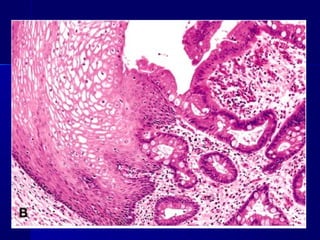

Squamous metaplasia

Anatomy of the cervix

METAPLASIAMETAPLASIA

 Es una alteración reversible en la que un tipoEs una alteración reversible en la que un tipo

celular maduro es sustituido por otro (epitelial ocelular maduro es sustituido por otro (epitelial o

mesenquimatoso)mesenquimatoso)

 Ejemplos: metaplasia escamosa, Esófago deEjemplos: metaplasia escamosa, Esófago de

Barret.Barret.

1. Metaplasias epiteliales:

Metaplasia epitelial escamosa: mucosas, conductos,

bronquios, cervix, endometrio y próstata.